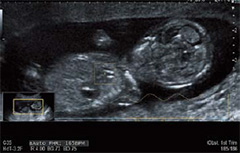

Auto FHR+

Bモード画像から胎児心臓の動きをリアルタイムにトラッキングし,胎児心拍数を自動計測します。ドプラ法やMモード法に比べ安全で客観的な計測ができます。経膣プローブでも計測可能で,極めて初期の段階から胎児の成長を確認することができます。